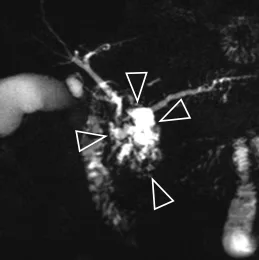

Figure 16. Exemple d’exploration par bili-IRM d’une volumineuse TIPMP de la tête du pancréas (têtes de flèches). Il s’y associe d’autres localisations corporéo-caudales de petite taille, et une augmentation de calibre du canal pancréatique principal